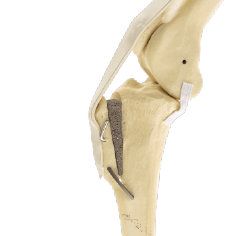

MMP ACL/CCL

The MMP CCL surgery redirects the force generated by the large quadriceps muscles to the patellar tendon to compensate for the failed cruciate ligament. This is achieved by moving forward the part of the tibia (the tibial tuberosity) attached to the quadriceps muscle. The patella tendon then acts in the same way that the previous CCL ligament did to stabilize the knee.